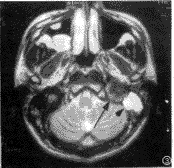

图2 与图1同一病例增强后,病灶明显强化(白箭)